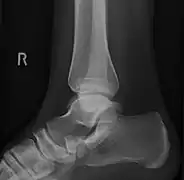

Lateral projection of type 2